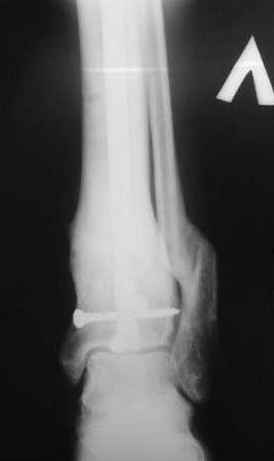

5, 6 - через 2,5 мес после травмы выполнен закрытый остеосинтез блокируемым штифтом.

7, 8, 9, 10, 11 - через 8 мес после травмы перелом сросся.

Пациент ходит без дополнительной опоры, не хромает (видеоролик выложил сюда